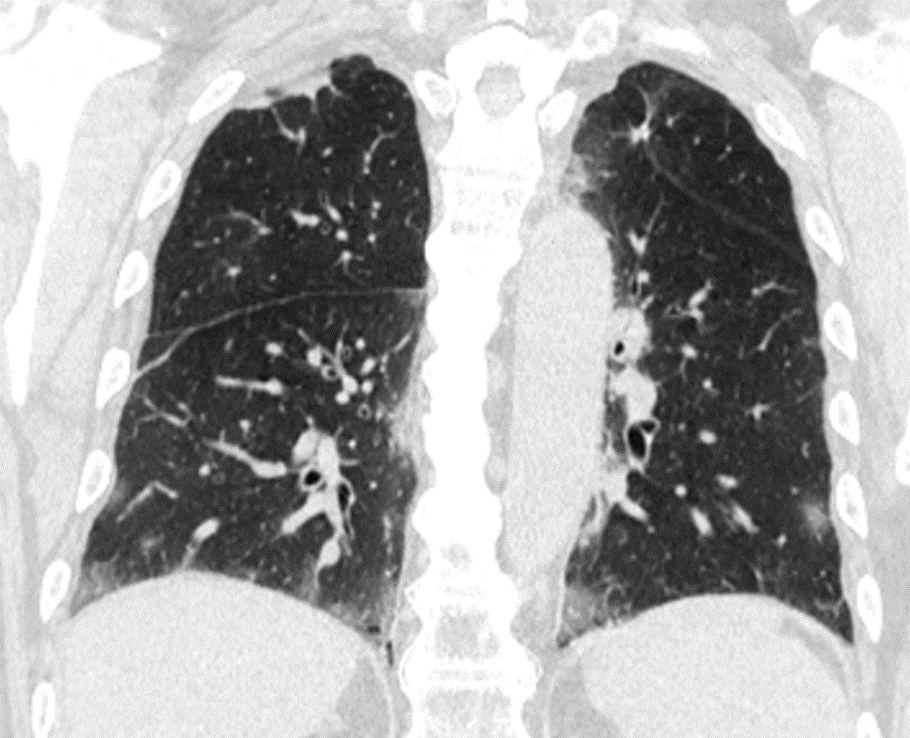

其实,这波omicron感染,确实肺炎比例比想象中要高,但很多都不会是大白肺,多数表现为双肺散发磨玻璃影,当然,也有单独的磨玻璃结节,特别容易表现为混合密度磨玻璃结节。其实很多新发的磨玻璃结节都是新冠肺炎,不用过于紧张,如果感染面积不大,一般临床上,也不需要特异性治疗,休息观察就行了。

可以考虑3个月以后复查一次薄层平扫CT。

CT提示,右肺下叶多发磨玻璃影。